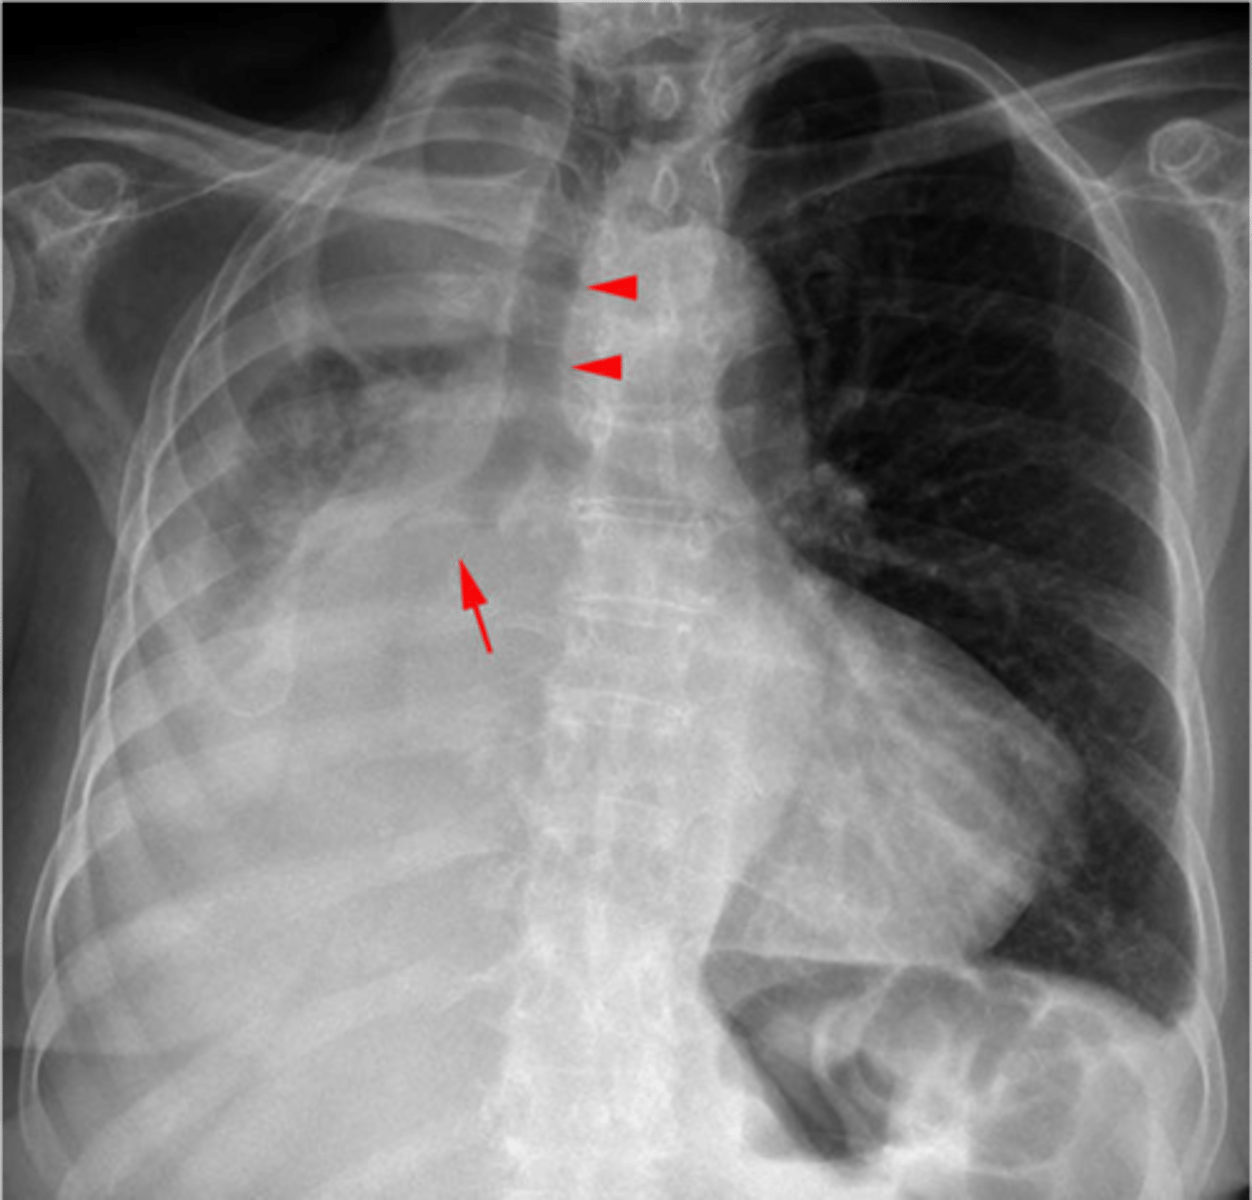

Tension pneumothorax

knowt flashcard image